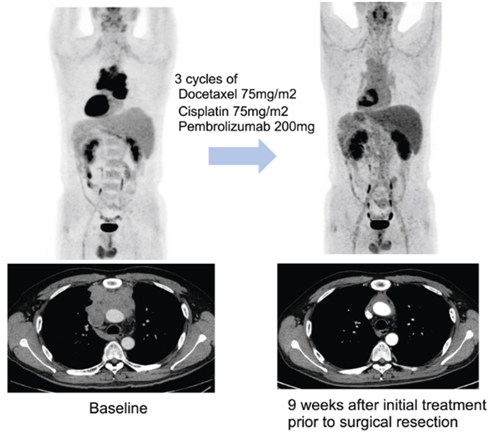

연구팀은 이들 환자에게 3주 간격으로 세 번에 걸쳐 기존 항암화학요법에 펨브롤리주맙을 병용 투여한 다음 수술 가능 여부를 평가했다. 수술 후에는 최대 32주간 펨브롤리주맙 유지하는 한편, 일부는 항암방사선치료를 더하는 식으로 치료가 진행됐다.

연구팀은 추적관찰 기간 27.5개월(중앙값) 동안 전체 환자의 57.5%(23명)에서 수술 전 치료를 통해 종양의 크기가 유의미하게 감소하는 반응을 보였다고 했다. 또한 82.5% 환자에서는 해당 치료로 인해 질병의 진행이 억제 되는 질병 조절이 관찰됐다고 전했다. 수술을 받을 만큼 암이 줄거나 반응을 보인 덕분에 전체 환자의 70%(28명)가 수술을 받았다고 밝혔다

치료 결과 병리 검사를 통해 암세포가 10% 이하로 감소한 지를 평가(MPR)했을 때 전체 환자의 32.5%(13명)가 도달한 것으로 나타났다. 당초 기대치 50%에는 미치지 못했지만, 수술 환자 놓고 보면 MPR 도달 비율은 46.4%로 증가해 펨브롤리주맙이 흉선상피종양 치료 선택지에 포함될 가능성에 파란불이 켜졌다.

박성용 교수는 “흉선상피종양 중에서도 예후가 비교적 좋다고 알려진 흉선종보다 예후가 나쁜 흉선암에서 치료 반응이 좋았다”면서 “수술이 어려웠던 환자에게 수술할 수 있게 될 경우 더 나은 예후를 기대할 수 있을 것”이라고 말했다.